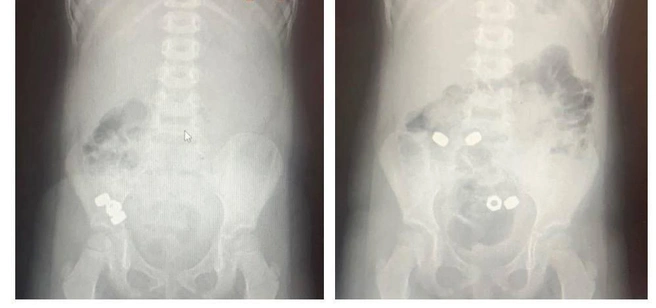

В больницу ребенка привезли родители. Они не были уверены, действительно ли мальчик проглотил детали. Для этого маленькому пациенту сделали рентген, который выявил в ЖКТ ребенка 16 маленьких гаек.

«Учитывая, что инородные тела были не инертные и не магнитные, врачи выбрали консервативную тактику: назначили диету, покой, контроль стула и рентгенографию в динамике», — рассказали в больнице.

В течение трех дней все проглоченные мальчиком гайки вышли из организма естественным путем, ребенка выписали.